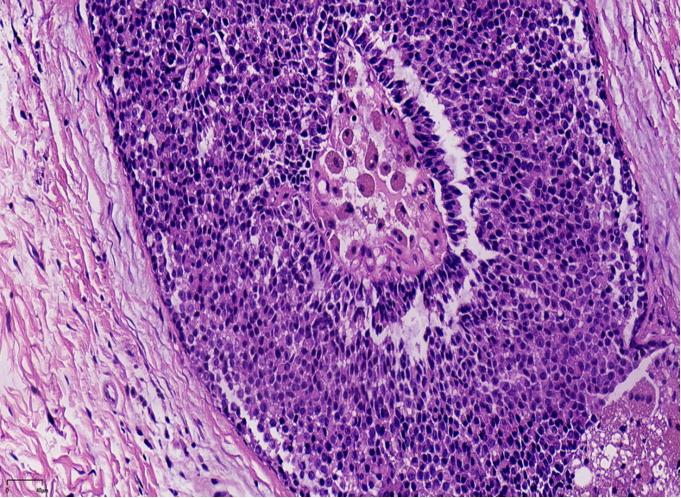

DCIS样,界限清楚、多个、膨胀性结节状

纤细的血管轴心周围细胞呈栅栏状排列

SPF细胞形态

特征性细胞:形态多样,卵圆形,梭形,多边形,印戒样或浆细胞样胞浆嗜酸性颗粒状,单形性,核低至中级别,染色细腻,可见小核仁核分裂少见(<5/10HPF)肿瘤细胞可有细胞内、外粘液形态单一,呈圆/卵圆形,胞浆淡染、嗜酸性颗粒状嗜酸性颗粒状

胞浆嗜酸性颗粒状胞浆,浆细胞样外观

原位SPC:轮廓光滑的圆形结节结节周围无促结缔组织增生结节周围肌上皮可有可无